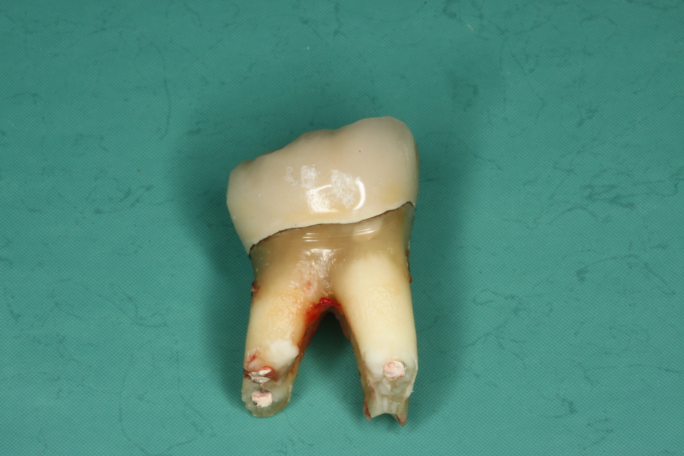

Die Entfernung wurzelkanalbehandelter Zähne in unserer Praxis

Der Austausch wurzelbehandelter und toter Zähne erfolgt so schonend wie möglich. An die Stelle des toten bzw. wurzelbehandelten Zahnes wird direkt in derselben Behandlung ein Keramikimplantat gesetzt, wenn genug gesunder Knochen vorhanden ist.